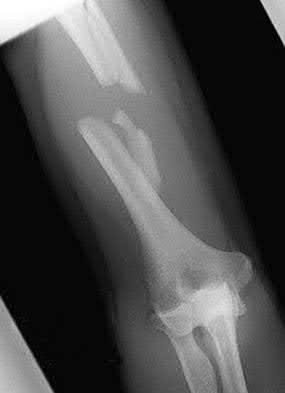

A 25-year-old female is involved in a motor vehicle collision. She presents with the isolated injury seen in Figures A through D. Her leg is swollen but her skin is intact. She has no clinical signs of compartment syndrome. Which of the following treatment options will allow for maintenance of fracture alignment and minimize the risk of soft tissue complications?

The patient presents with a closed distal third metaphyseal-diaphyseal distal tibia fracture with simple intra-articular extension. Immediate intramedullary nailing along with percutaneous fixation of the articular component provides appropriate restoration of length, rotation and alignment and minimizes the risk of wound complication.

Displaced distal third tibia fractures may be associated with simple intraarticular extension. Operative treatment of intra-articular distal tibia fractures has historically been performed with open reduction and internal fixation. Early open reduction and plate fixation of pilon fractures has been associated with high rates of infection and wound complication. In select patterns with simple articular extension, percutaneous screw fixation and medullary nailing may provide appropriate reduction with minimal soft-tissue risk.

Figures A and B demonstrate a distal third tibial shaft fracture with simple intra-articular extension. The axial and coronal CT cuts in Figures C and D further clarify the articular injury. Illustrations A and B demonstrate a comminuted distal third tibial fracture with simple intra-articular extension. Illustrations C and D are fluoroscopic images of the same injury after intramedullary nailing and percutaneous fixation of the articular component.